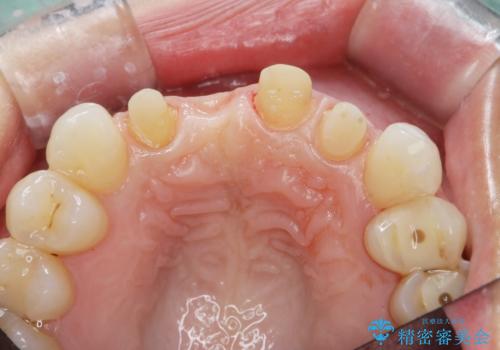

- 前医に前歯の吸収による抜歯の必要性を伝えられ、前歯の審美的な改善・治療を求めて来院されました。

CT撮影を行った結果、右上前歯は吸収が進み抜歯が必要な状態です、

抜歯をせず放置すると、より吸収が進み臨在する歯にも悪影響を及ぼしてしまう可能性が考えられます。

上顎4前歯は、根管治療の既往があり、虫歯も見られたことからブリッジによる治療で審美性の回復を行うとともに臨在歯の虫歯もセラミック治療を行っていきます。